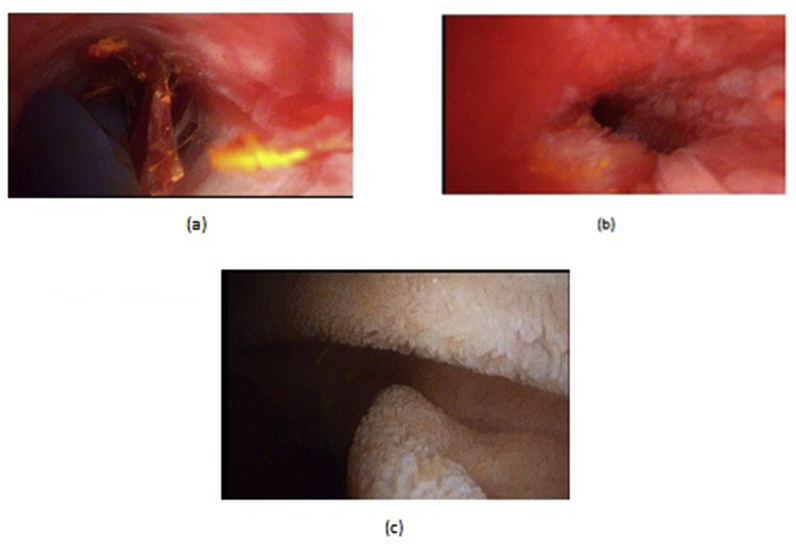

LCD: Under general anesthesia; we used the standard four-port technique of LC. Routine trans-cystic intra-operative cholangiography (IOC) was performed in all cases for identification of stones number, site and size. The gallbladder was left in situ for retraction until the operation was completed. When we reached CBD, a longitudinal supraduodenal choledochotomy(1.5–2 cm) was done using scissors or cautery. The CBD stones were entirely retrieved in all patients using cholecodoscopic extraction techniques (4.5-Fr flexible choledochoscope; Karl Storz, Tuttlingen, Germany) by irrigation, balloon or basket with mechanical lithotripsy when needed. The epigastric port was used to accommodate the operating choledochoscope [ref. 15,ref. 18,ref. [26], ref. [27], ref. [28], ref. [29]]. After all stones were retrieved and clearance of the bile duct was confirmed with choledochoscopy, the choledochotomy was closed with interrupted 4.0 Vicryl sutures in patients with primary closure of CBD and then IOC was done through the cystic duct to confirm absence of stones and leak (Fig. 1). On the other hand, for patients with T-tube drainage, the T-tube was placed in the choledochotomy and secured with sutures, Patients had a cholangiogram on the 6th postoperative day. If the finding was normal, the T-tube was clamped and patients were discharged home with the T-tube in situ then it was removed from 4 to 6 weeks later after normal tube cholangiogram in the outpatient clinic. [ref. 23,ref. 27,ref. 30]. Lastly, laparoscopic HJ was done by 4.0 polydioxanone (PDS) sutures (posterior and anterior interrupted sutures) and a tube drain was placed near the anastomosis and removed days after the operation (Fig. 2) [ref. 1,ref. 14,ref. 31,ref. 32].

OCD: It started by open cholecystectomy (OC) and IOC through the cystic duct; then identification of CBD and the junction between the cystic duct and the CBD were done. A complete Kocher’s maneuver was performed in order to feel the retro- and intra-pancreatic portion of the CBD for easy extraction of stones and to feel the papilla. Then, two stay sutures were placed transversally at the right and left portions of the duct; then the anterior wall of the supraduodenal part of CBD was opened. The incision was performed with a sharp scalpel, then an exploration of the CBD first proximally and then distally with the Randall forceps occurred for extraction of visible stones. The proximal and distal CBD was then irrigated with saline using a soft catheter. In choledochoscopic cases, the CBD stones were entirely retrieved using choledochoscopic extraction techniques (4.5-Fr flexible choledochoscope; Karl Storz, Tuttlingen, Germany) (Fig. 5, Fig. 6). After all stones were extracted and clearance of the bile duct was confirmed; the management was as mentioned in LCD (Fig. 3, Fig. 4). Lastly, in HJ cases, the biliary-enteric anastomosis was done by 4.0 PDS sutures (posterior continuous and anterior interrupted sutures) [ref. 20].

TDS (for impacted stones in the ampulla of Vater): A Kocher maneuver was performed, after which a longitudinal anterior duodenotomy was made at the level of the ampulla, the ampulla and distal CBD were divided for a distance of 1.5–2 cm, directed anteromedially. The sphincter was divided sequentially between small clamps, with sequential suture approximation of the duodenal and bile duct mucosa using fine interrupted absorbable suture 4.0 vicryle. The duodenum was then closed transversely [ref. 8,ref. 33].